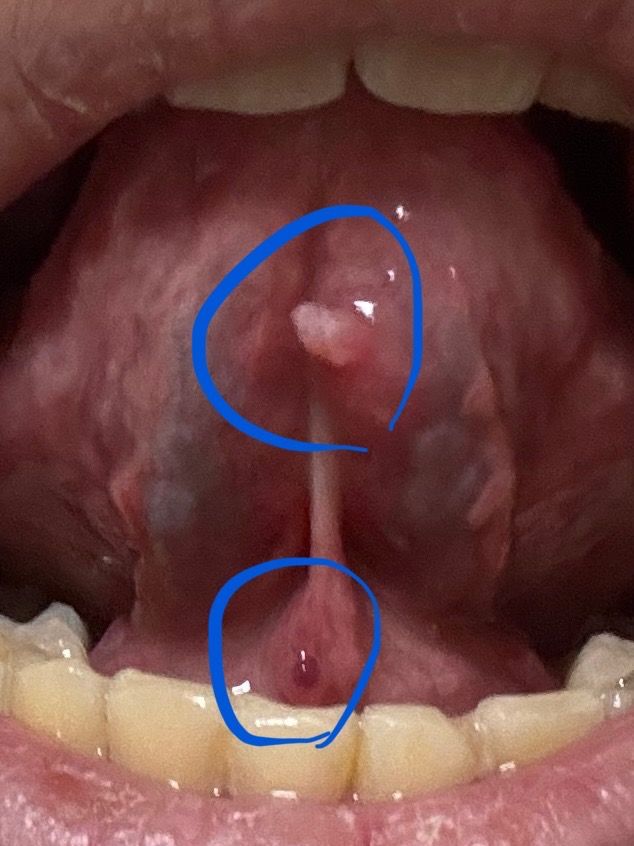

이거 입에 난 거 뭔지 아는 의사분 계신가요?

징그러운 사진이라 죄송합니다.

이틀 전에 입에 뭐가 나서 보니 저런게 낫더라고요.

일단 통증은 없고 최근에 성관계도 없었습니다.

무슨 병일까요?

두 병변 모두 돌출된 점막 병변으로 가장 가능성 높은 것은 점액낭종 계열 병변입니다. 침샘(소타액선)이 일시적으로 막히거나 미세한 외상·자극 이후 점액이 고여 생기는 것으로, 통증이 없고 갑자기 생기는 경우가 흔합니다. 위쪽 하얀 돌출, 아래쪽 붉은 돌출 모두 같은 기전으로 설명이 됩니다.

성병성 병변, 아프타성 궤양, 악성 병변의 전형적인 양상과는 거리가 있습니다. 대부분 1~2주 내 크기가 줄거나 자연 소실됩니다. 다만 크기가 커지거나 단단해짐, 출혈, 2주 이상 지속 시에는 구강외과 또는 이비인후과에서 확인이 필요합니다.